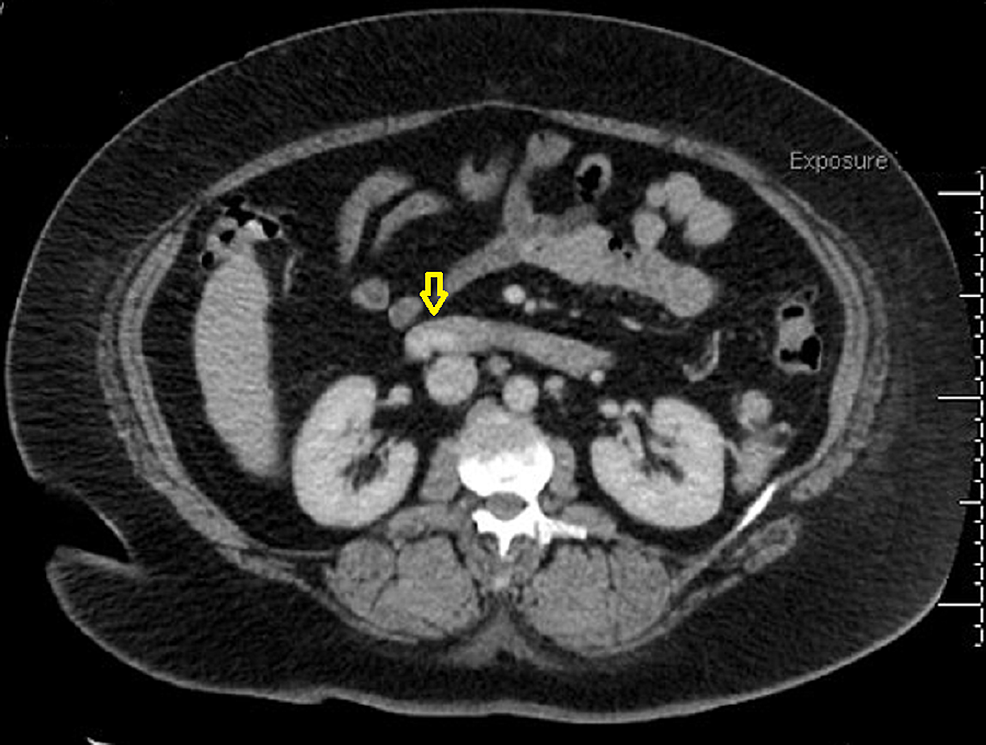

Endoscopic Band Ligation of Bleeding Duodenal Varices Cureus

Endoscopic Band Ligation of Bleeding Duodenal Varices Cureus Endoscopic Of Band Ligation endoscopic variceal ligation (evl) was developed in an effort to find an effective endoscopic treatment for. 3 endoscopic band ligation is now established as. endoscopic band ligation (ebl) is the initial treatment of choice in the management of acute esophageal variceal bleeding. endoscopic band ligation (ebl) has been proposed as a safe and effective endoscopic treatment with. Endoscopic Of Band Ligation.

Figure 3 from Endoscopic Band Ligation of Bleeding Duodenal Varices Endoscopic Of Band Ligation 3 endoscopic band ligation is now established as. endoscopic band ligation (ebl) has been proposed as a safe and effective endoscopic treatment with a high success. band ligation is one of the mechanical hemostatic procedures used to control both upper and lower gi bleedings. endoscopic variceal ligation (evl) was developed in an effort to find an effective. Endoscopic Of Band Ligation.